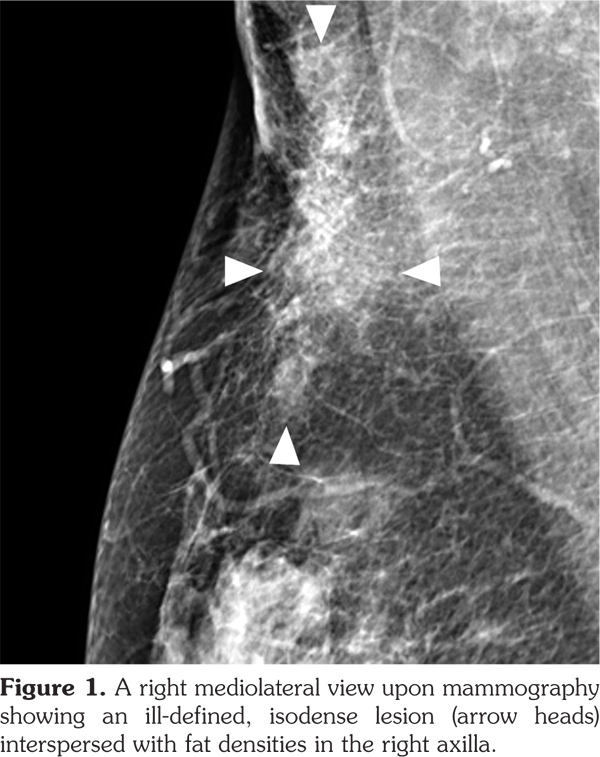

Full-field digital mammography was performed (MAMMOMAT Inspiration; Siemens AG, Munich, Germany). A right mediolateral oblique view revealed an asymmetric density in the right axilla (Figure 1). Ultrasonography was performed with a 5- to 12-MHz linear transducer (iU22; Philips Medical Systems, Bothell, WA, USA), which identified a poorly defined, elongated, homogeneously hyperechoic lesion in the subcutaneous fat layer of the right axilla (Figure 2). The lesion did not exhibit increased vascularity, except for a normal traversing venous structure (Figure 2). The lesion was surgically excised. Pathological examination confirmed the diagnosis as lipogranuloma (Figure 3). On the other hand, complete blood test results were normal.